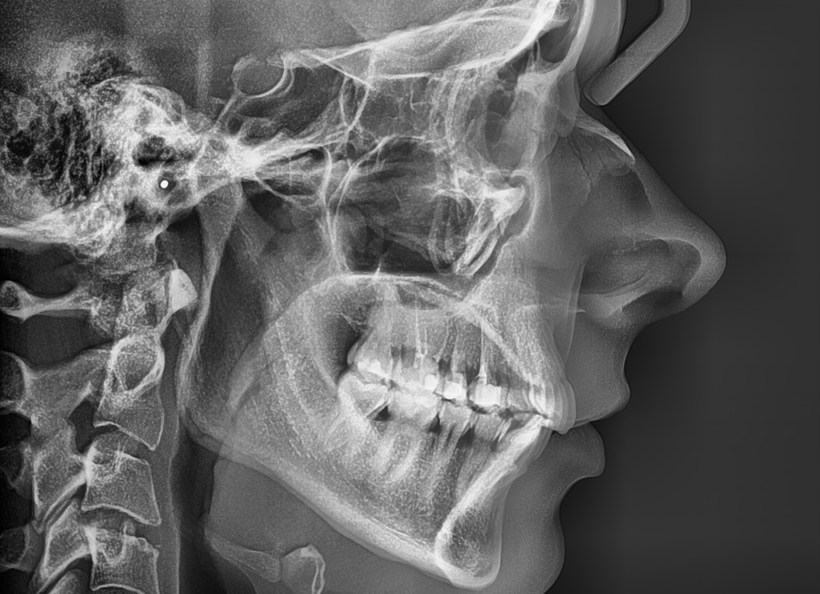

Teleradiografia (cefalometria) de profil

Teleradiografia de profil este radiografia în care se surprinde întregul craniu și este recomandată atunci când se dorește aplicarea unui aparat ortodontic. Se poate face examinarea dinților în legatură cu maxilarul și profilul pacientului.